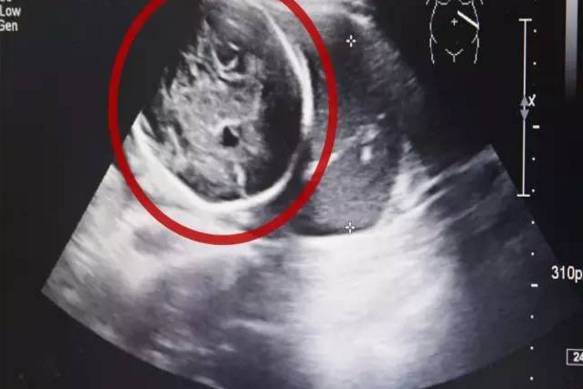

经B超检查,小芳竟然已经怀孕了,而且胎儿已经长到了6个多月!但是让人震惊的是胎儿并没有长在子宫里,而是长在了腹腔内。医生确诊小芳为“腹腔妊娠”,也就是宫外孕的一种,这种发病率约为1:15000,母体死亡率约为5%,胎儿存活率仅为1%的罕见妊娠,竟然发生在了她的身上,而且小芳已经出现肚子疼痛,情况十分紧急!

医院妇产科的医生说:这种异位妊娠就像体内的一个‘定时炸弹’,随时可能破裂大出血危及生命。”